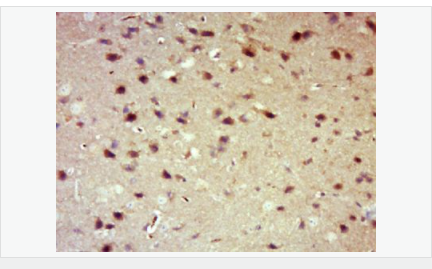

| 產(chǎn)品應用 | WB=1:500-2000 IHC-P=1:100-500 IHC-F=1:100-500 Flow-Cyt=1μg /test. IF=1:100-500 (石蠟切片需做抗原修復) not yet tested in other applications. optimal dilutions/concentrations should be determined by the end user. |

| 產(chǎn)品介紹 | 14-3-3 are activates tyrosine and tryptophan hydroxylases in the presence of Ca (2+)/calmodulin-dependent protein kinase II, and strongly activates protein kinase C. Is probably a multifunctional regulator of the cell signaling processes mediated by both kinases. Activates the ADP-ribosyltransferase (exoS) activity of bacterial origin. 14-3-3 proteins are localized in neurons, and are axonally transported to the nerve terminals. They may be also present, at lower levels, in various other eukaryotic tissues. It belongs to the 14-3-3 family. This antibody is reactive with 14-3-3 Alpha, Beta, Gamma, Delta, Epsilon. Function: Adapter protein implicated in the regulation of a large spectrum of both general and specialized signaling pathways. Binds to a large number of partners, usually by recognition of a phosphoserine or phosphothreonine motif. Binding generally results in the modulation of the activity of the binding partner. Subunit: Interacts with CDK16 and BSPRY. Interacts with WEE1 (C-terminal). Interacts with SAMSN1. Interacts with MLF1 (phosphorylated form); the interaction retains it in the cytoplasm. Interacts with Thr-phosphorylated ITGB2. Interacts with BCL2L11. Homodimer. Heterodimerizes with YWHAE. Homo- and hetero-dimerization is inhibited by phosphorylation on Ser-58. Interacts with FOXO4, NOXA1, SSH1 and ARHGEF2. Interacts with Pseudomonas aeruginosa exoS (unphosphorylated form). Interacts with BAX; the interaction occurs in the cytoplasm. Under stress conditions, MAPK8-mediated phosphorylation releases BAX to mitochondria. Interacts with phosphorylated RAF1; the interaction is inhibited when YWHAZ is phosphorylated on Thr-232. Interacts with TP53; the interaction enhances p53 transcriptional activity. The Ser-58 phosphorylated form inhibits this interaction and p53 transcriptional activity. Interacts with ABL1 (phosphorylated form); the interaction retains ABL1 in the cytoplasm. Interacts with PKA-phosphorylated AANAT; the interaction modulates AANAT enzymatic activity by increasing affinity for arylalkylamines and acetyl-CoA and protecting the enzyme from dephosphorylation and proteasomal degradation. It may also prevent thiol-dependent inactivation. Interacts with AKT1; the interaction phosphorylates YWHAZ and modulates dimerization. Interacts with GAB2 and TLK2. Subcellular Location: Cytoplasm. Melanosome. Note=Located to stage I to stage IV melanosomes. Post-translational modifications: The delta, brain-specific form differs from the zeta form in being phosphorylated. Phosphorylation on Ser-184 by MAPK8; promotes dissociation of BAX and translocation of BAX to mitochondria. Phosphorylation on Ser-58 by PKA; disrupts homodimerization and heterodimerization with YHAE and TP53. This phosphorylation appears to be activated by sphingosine. Phosphorylation on Thr-232; inhibits binding of RAF1. Similarity: Belongs to the 14-3-3 family. SWISS: P31946 Gene ID: 7529 Database links: Entrez Gene: 7529 Human Entrez Gene: 54401 Mouse Omim: 601289 Human SwissProt: P31946 Human SwissProt: Q9CQV8 Mouse Unigene: 643544 Human Unigene: 34319 Mouse Unigene: 485025 Mouse Unigene: 8653 Rat Important Note: This product as supplied is intended for research use only, not for use in human, therapeutic or diagnostic applications. 信號傳導(Signaling Intermediates) 14-3-3蛋白是一個涉及調(diào)節(jié)細胞凋亡、促細胞分裂信號傳導和細胞周期關(guān)卡的蛋白質(zhì)家族。它被認為是通過與絲氨酸殘基磷酸化的蛋白質(zhì)的結(jié)合介導的信號傳導中的關(guān)鍵調(diào)節(jié)物。通過與Bad(相關(guān)死亡因子)的結(jié)合, 14-3-3 蛋白由于將Bad隔離于胞液而防止了細胞凋亡。 蛋白是14-3-3家族成員。它廣泛分布于哺乳動物、兩棲類、昆蟲、植物和酵母菌的真核生物高度保守性多功能蛋白質(zhì)。 目前已知至少有16個成員。此抗體識別分子量為30-31kDa的14-3-3蛋白αβγδε亞型。 |